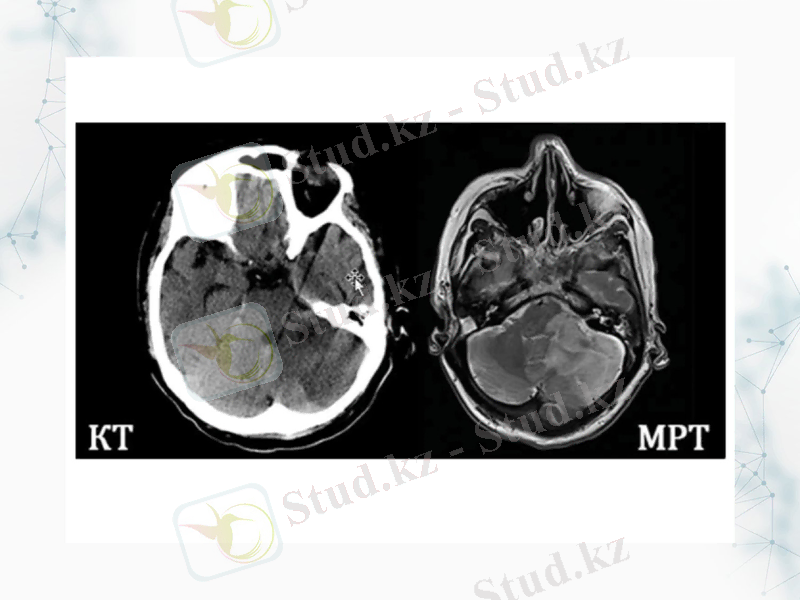

Мидың қан тамырлық аурулары қан құйылу, геморрагиялық және ишемиялық инсульт

Ішкі қан ағумен көрінетін бас миының жарақаты мен бас миының соғылуы